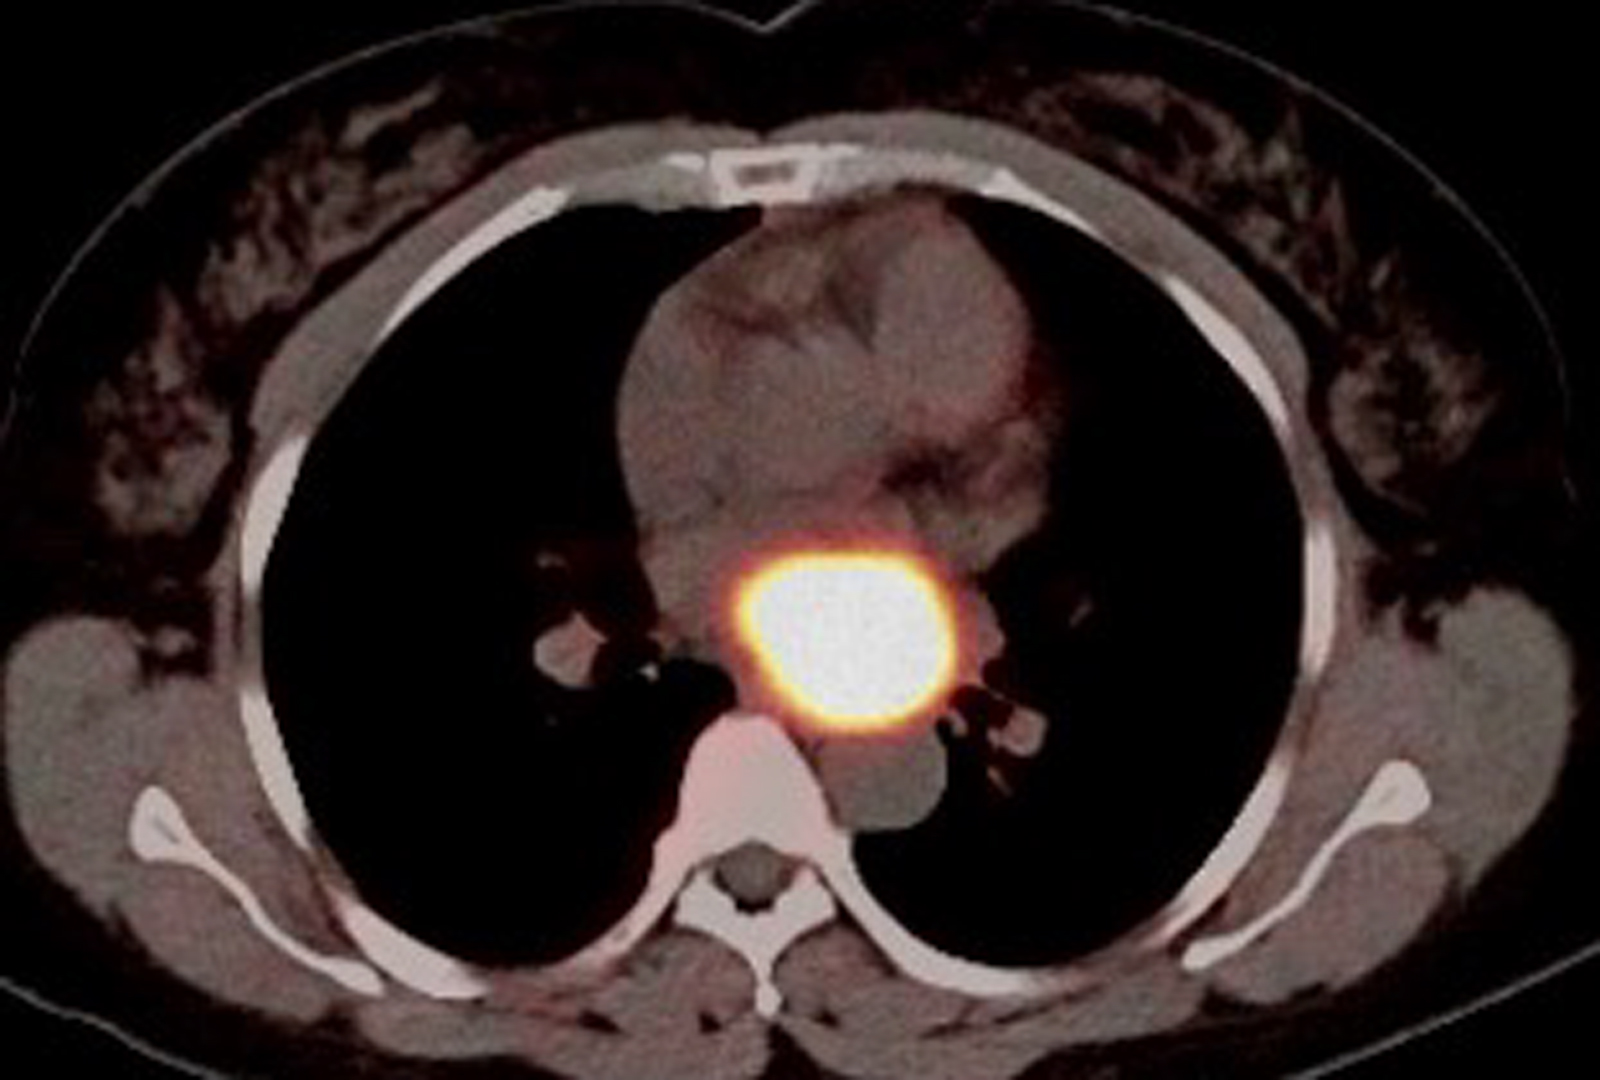

The patient presented with heart palpitations. Initial imaging revealed a large mediastinal mass above the left atrium extending into the subcarinal region with features suggestive of a paraganglioma—a rare neuroendocrine tumor that arises from extraadrenal chromaffin cells.

PET scan showing intense somatostatin receptor (SSTR) expression consistent with paraganglioma. Source: NYU Langone Health